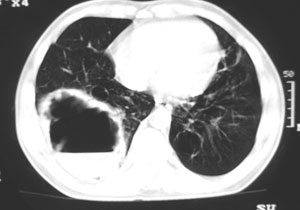

以下是引用卜一在2006-8-26 15:32:00的发言:[br]右下肺巨大气液囊肿,局部与支气管相同,壁厚薄不均,周围见渗出性病变,相应胸膜增厚.多考虑:支气管囊肿合并感染.

以下是引用liuyue在2006-8-26 17:31:00的发言:[br]右上肺可见多个小囊状无肺纹理影,左上肺亦见一个小囊状无肺纹理影,边缘清楚;右下肺巨大囊肿,内部可见液气平面,壁厚薄不均,周围见渗出性病变,相应胸膜增厚.考虑:1多发性支气管囊肿2右下肺支气管囊肿合并感染.